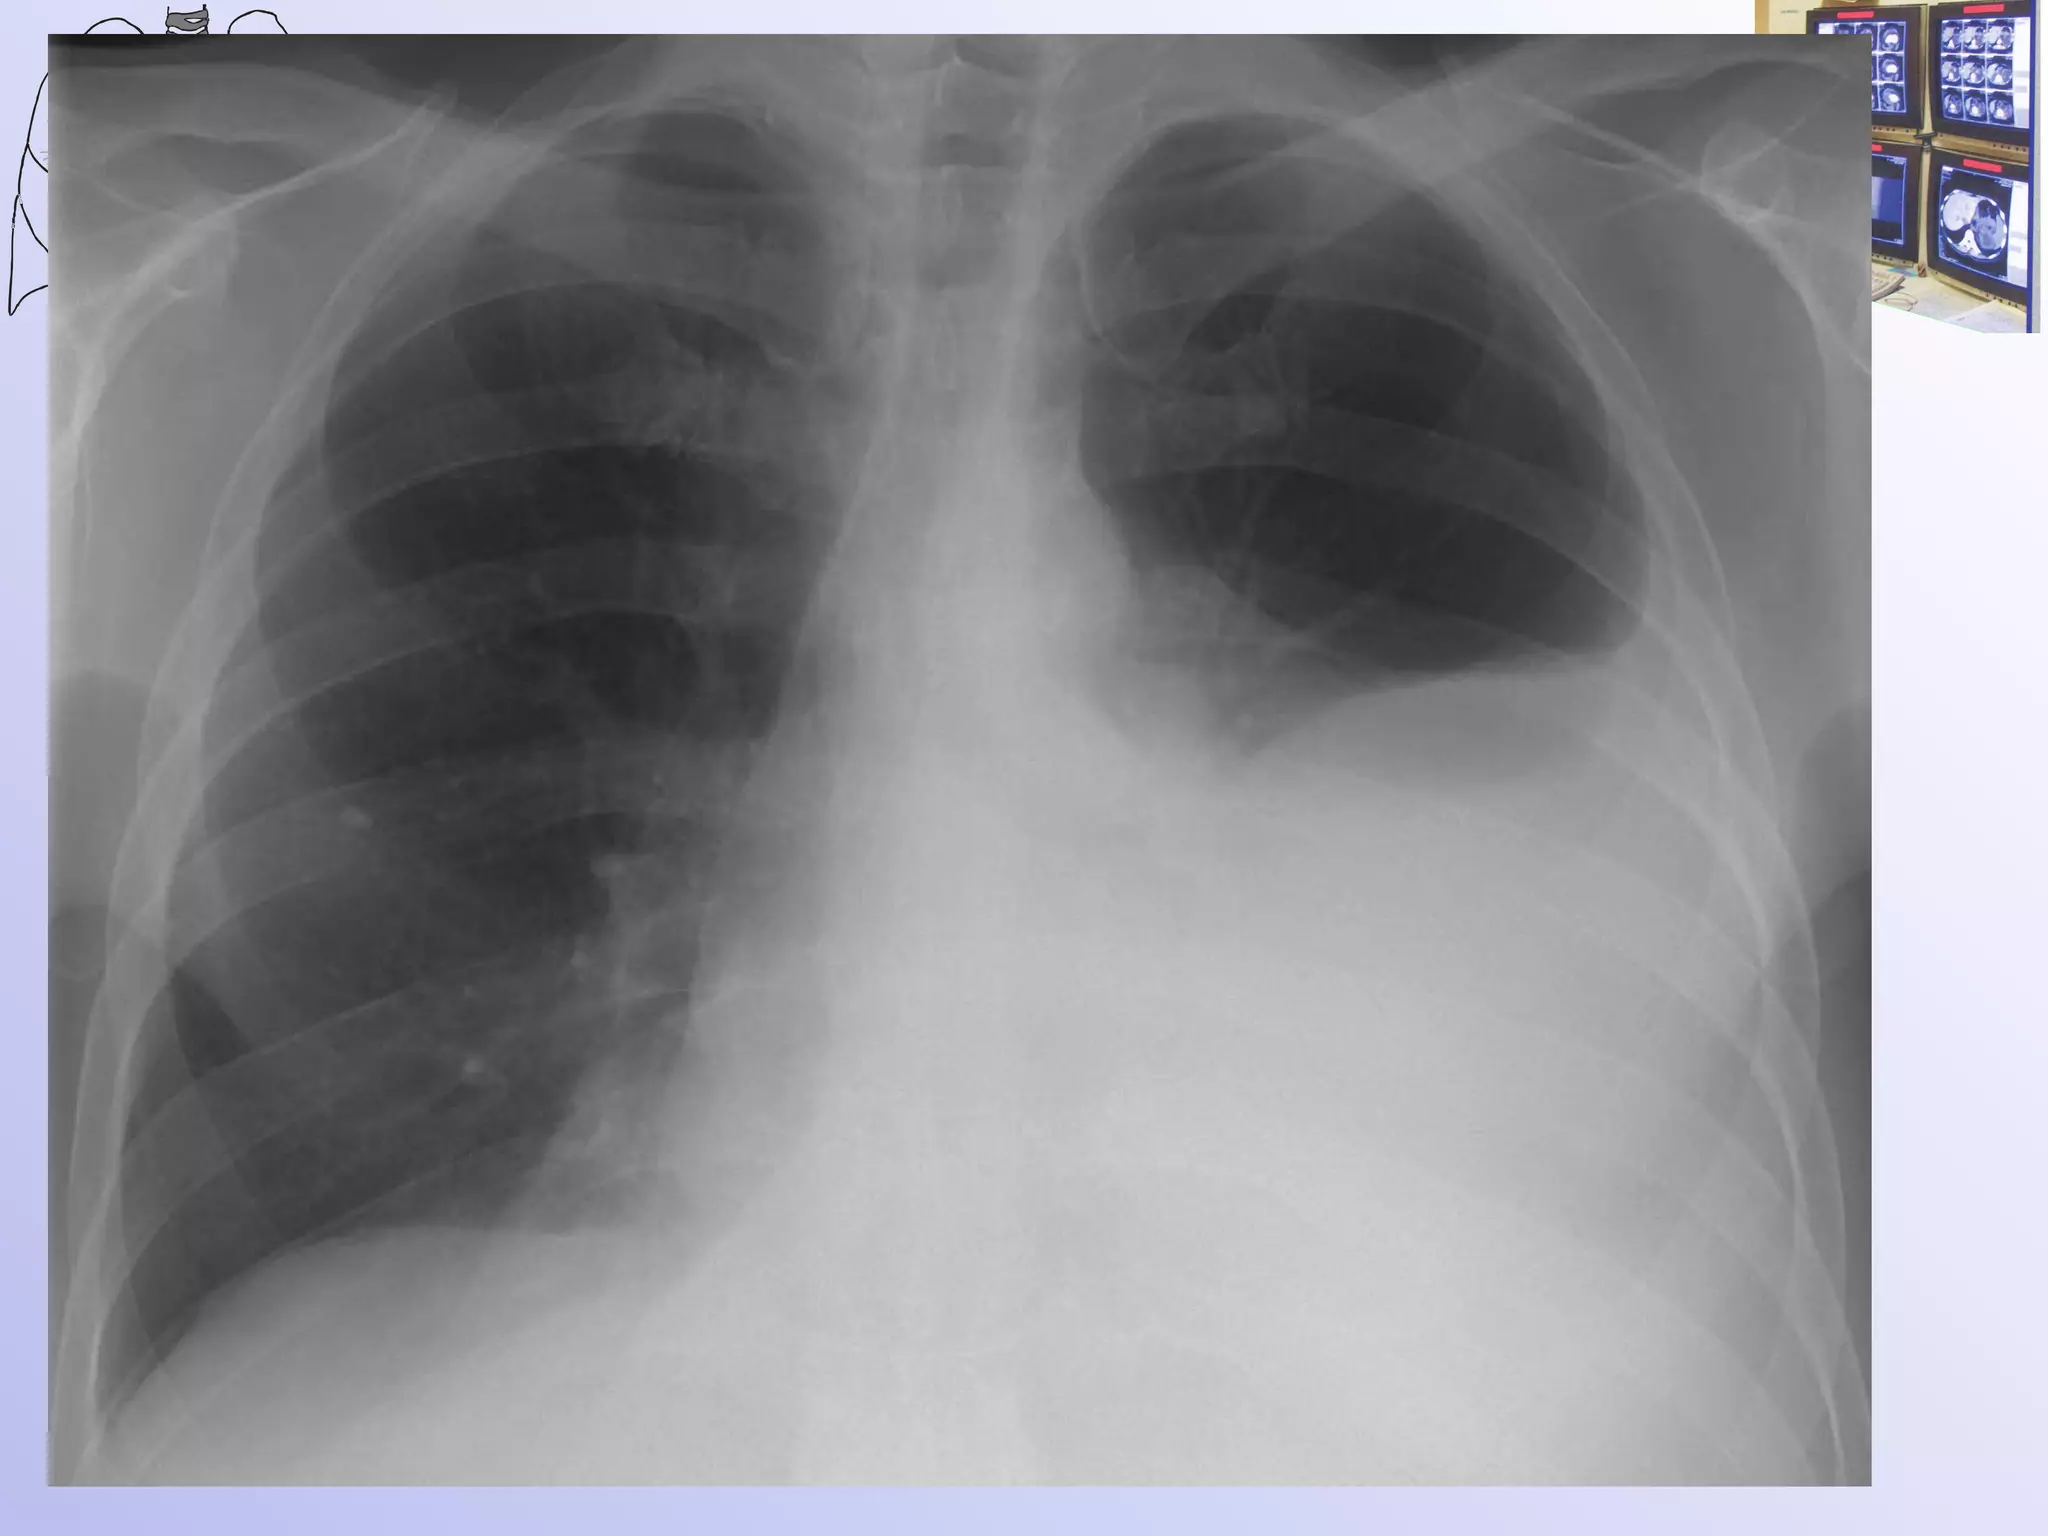

Ателектаз? Плеврит?

После пункции